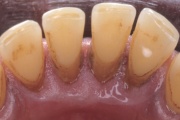

Krooniline parodontiit

Krooniline parodontiit on mikroobide poolt põhjustatud hammaste tugikudede põletik, mille tulemusena tekib progresseeruv alveolaarluu (nähtav röntgenograamil) ja periodontaalligamendi destruktsioon, igemetaskute moodustumine, igeme retsessioon või mõlemad kahjustused kombineeritult. Loe edasi »

- igemepealne hambakivi (5)

- igemealune hambakivi (4)